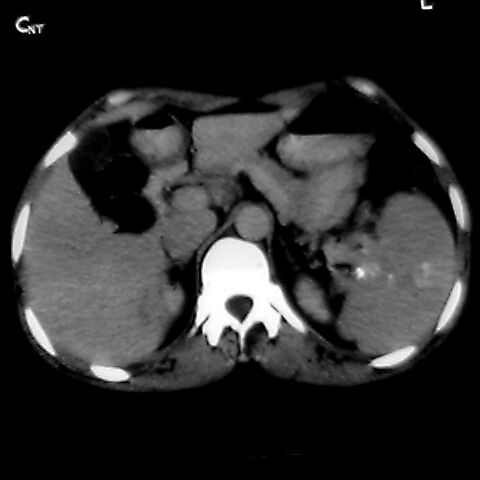

女 48岁 食道癌术前体检发现脾占位。

脾胀内部巨大低密度肿块,边界清或不清,中心坏死,轻度增强,内见散在钙化,结合食道癌病史多考虑:转移癌.

1肝右下叶小囊肿2右肾上极囊肿或错构瘤3脾脏不典型血管瘤可能性大.

脾脏低密度灶伴钙化,增强化明显,中心见液化坏死灶,强化延时明显。考虑血管瘤。转移瘤待排。